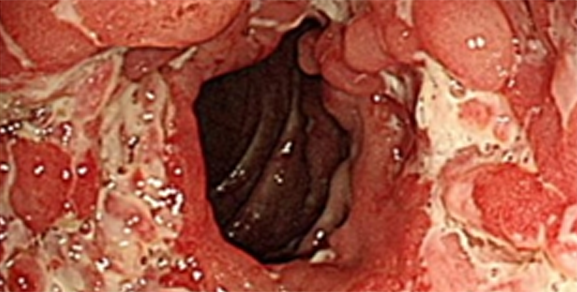

궤양성 대장염이 심화된 상태 대장내시경과 조직검사를 통해 진단합니다.

주로 내시경 소견 상 미만성, 표재성 궤양, 연속성 병변이 보이며 대부분 직장을 침범한 형태입니다.

병변부위는 직장 및 S상 결장염, 좌측결장염, 광범위 대장염으로 분류할 수 있습니다.